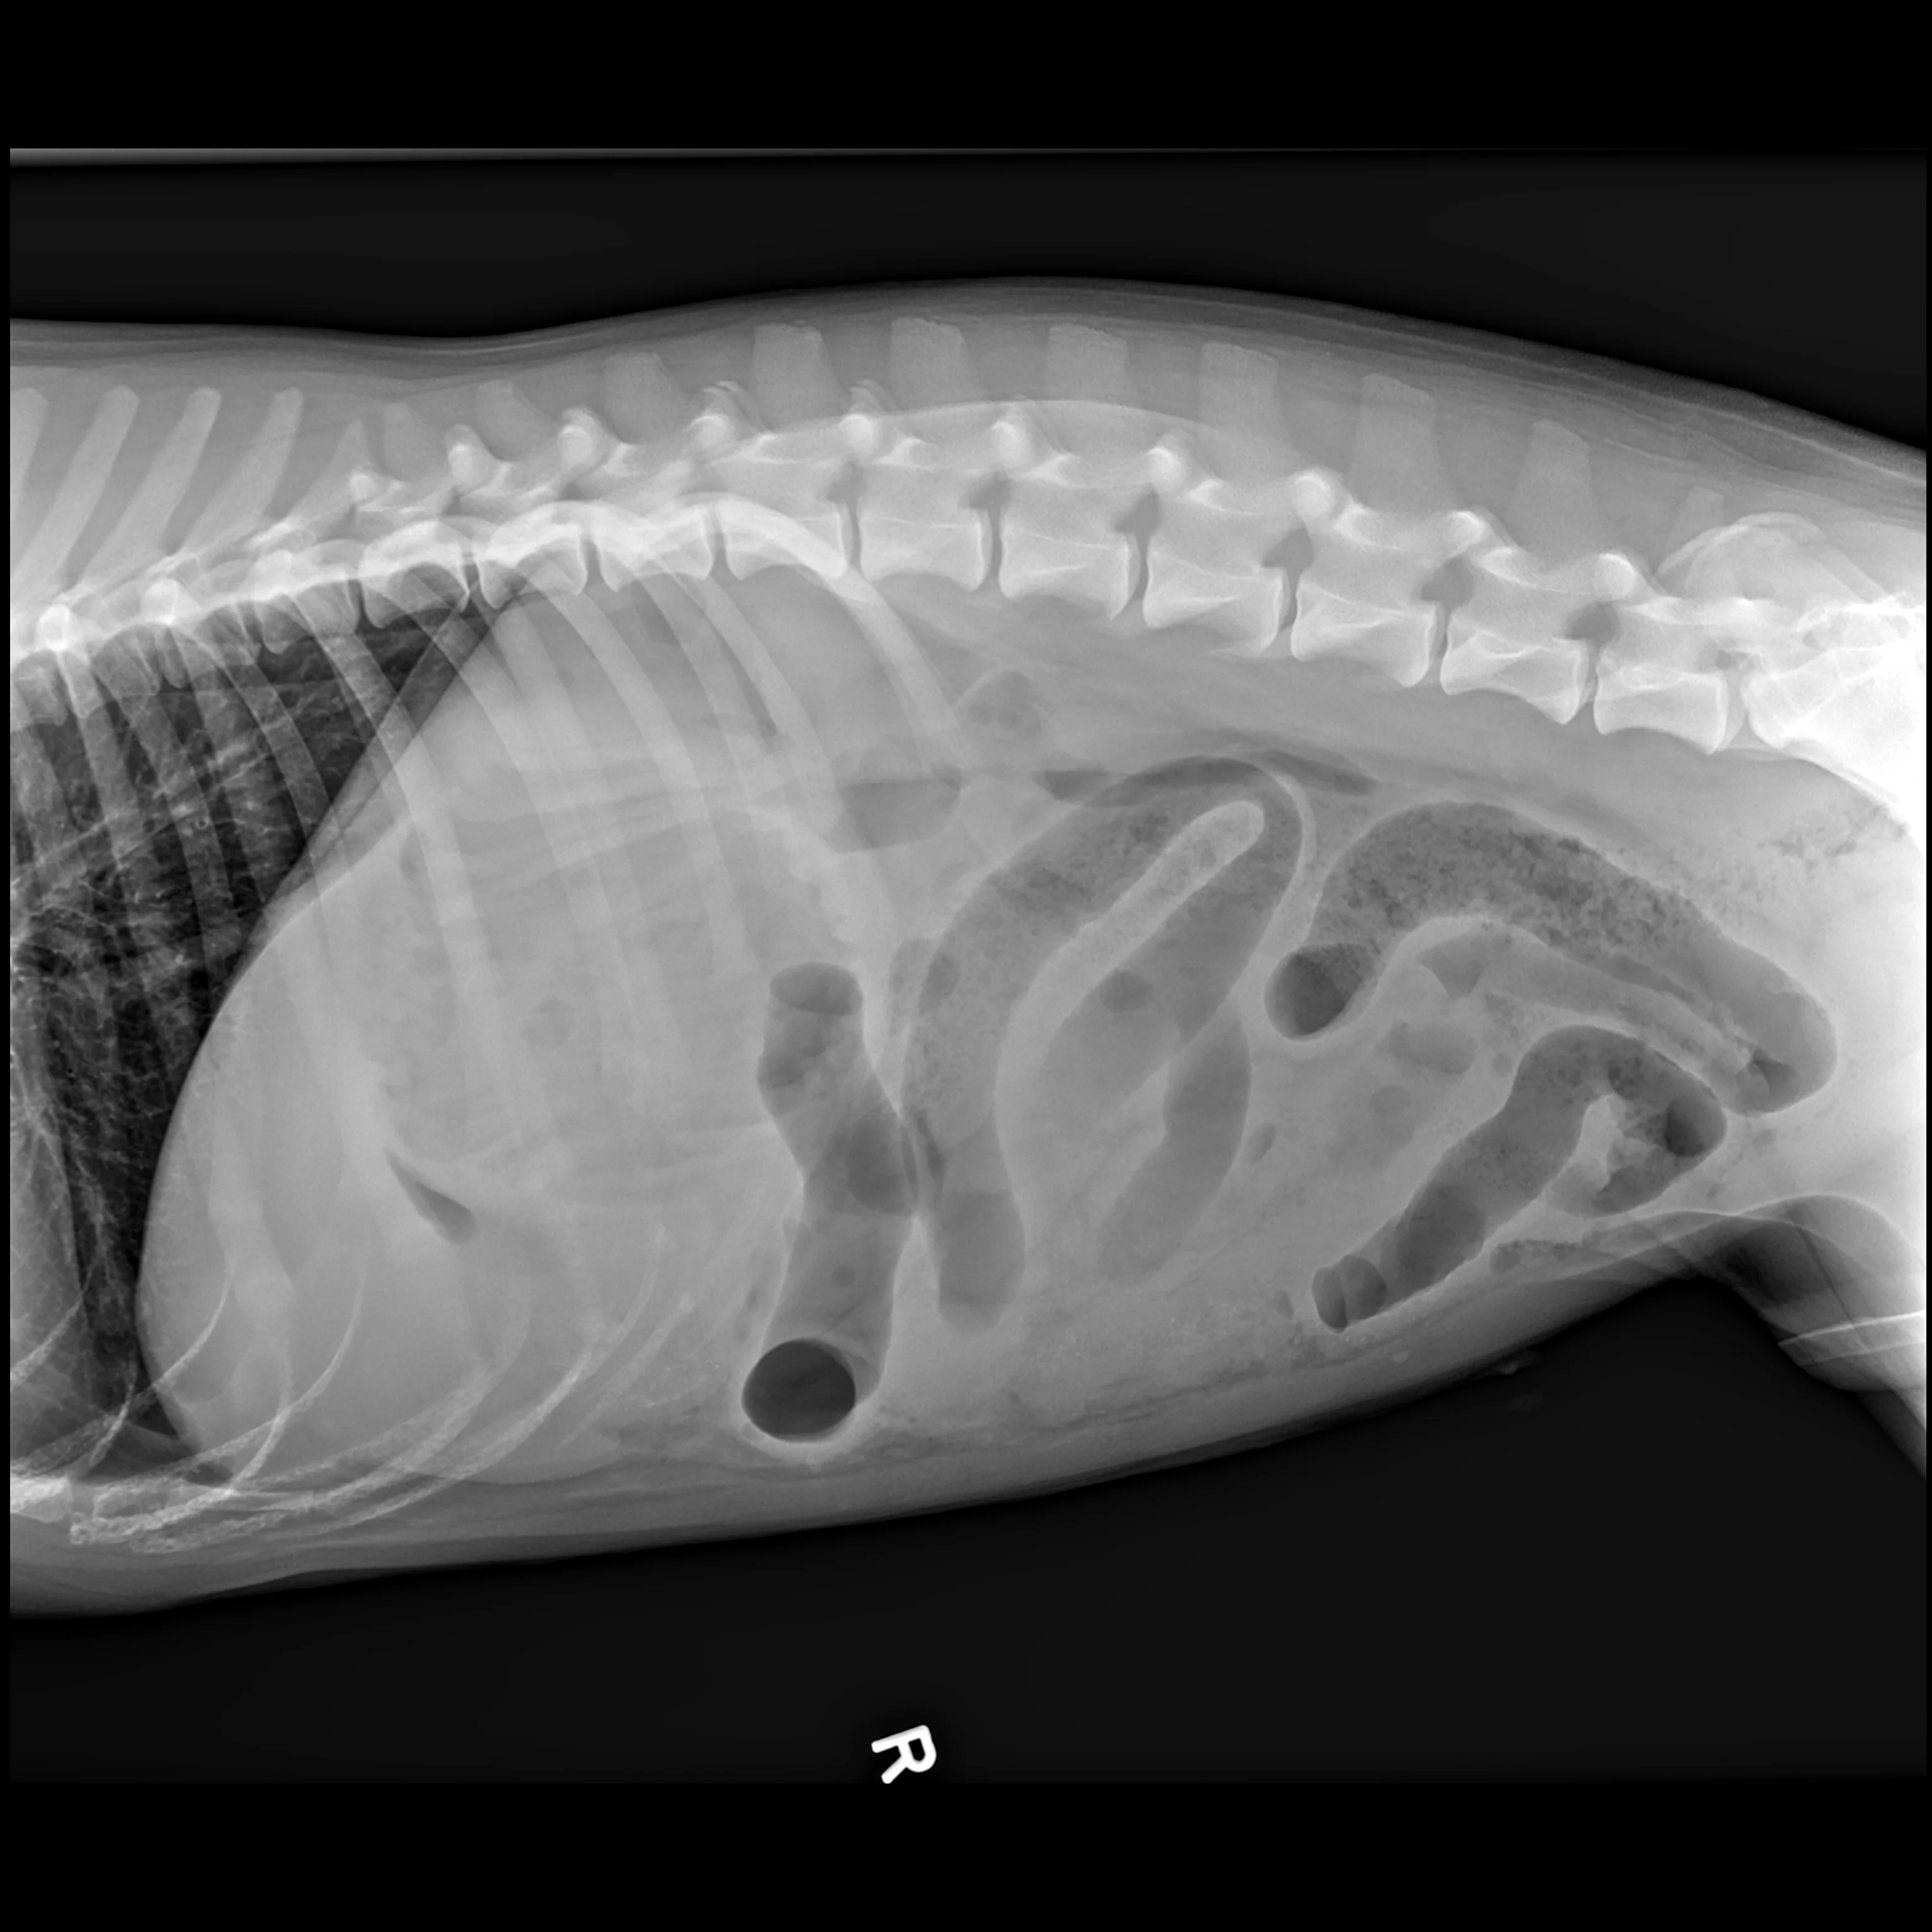

A complete radiographic study includes left lateral, ventrodorsal, and right lateral projections. Obtaining a left lateral projection and performing projections in the aforementioned order can improve visualization of the pylorus and duodenum by shifting gas into the lumens.3 Normal intraluminal gas is an in vivo negative contrast agent that can make soft tissue opaque foreign bodies (eg, cloth) easier to see (Figure 1).

Three-view abdominal radiographs of a 6-year-old spayed dachshund with an acute pyloric outflow obstruction secondary to a surgically confirmed foreign body (cloth). The stomach (pound signs) is moderately dilated with gas and fluid. On the left lateral and ventrodorsal projections, gas outlines an irregularly shaped soft tissue opaque foreign body (arrows) within the pylorus that extends into the duodenum. On the right lateral projection, the foreign body is more difficult to see because it is surrounded by similarly opaque gastric fluid.